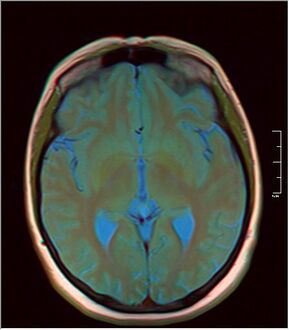

كيسة الغدة الصنوبرية pineal gland cyst هو تكيّس حميد (غير خبيث) في الغدة الصنوبرية، a small endocrine gland in the brain. Historically, these fluid-filled bodies appeared on 1-4% of magnetic resonance imaging (MRI) brain scans, but were more frequently diagnosed at death, seen in 4-11% of autopsies.[1] A 2007 study by Pu et al. found a frequency of 23% in brain scans (with a mean diameter of 4.3 mm).[1]